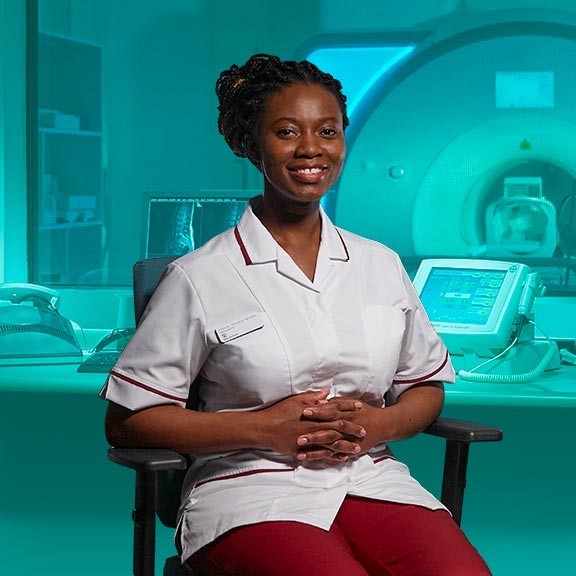

MRI scans

Spire London East Hospital offers a high quality, comfortable and fast MRI scanning service. We offer appointments to fit around you.